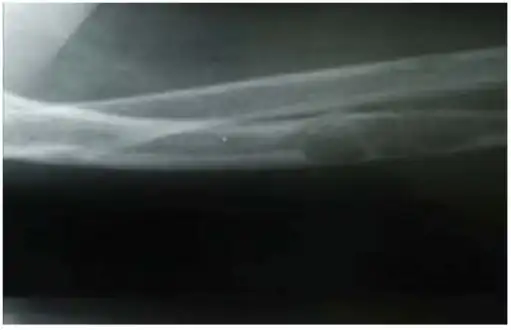

- Lateral X-ray of the right radioulna showing osteitis fibrosa cystica lesion of ulna diaphysis with a pathologic fracture

The major symptoms of OFC are bone pain or tenderness, bone fractures, and skeletal deformities such as bowing of the bones. The underlying hyperparathyroidism may cause kidney stones, nausea, constipation, fatigue and weakness. X-rays may indicate thin bones, fractures, bowing, and cysts. Fractures are most commonly localized in the arms, legs, or spine.[2][3]

X-rays may also be used to diagnose the disease. Usually, these X-rays will show extremely thin bones, which are often bowed or fractured. However, such symptoms are also associated with other bone diseases, such as osteopenia or osteoporosis.[29] Generally, the first bones to show symptoms via X-ray are the fingers.[22] Furthermore, brown tumors, especially when manifested on facial bones, can be misdiagnosed as cancerous.[29] Radiographs distinctly show bone resorption and X-rays of the skull may depict an image often described as "ground glass" or "salt and pepper".[30][31] Dental X-rays may also be abnormal.[2]